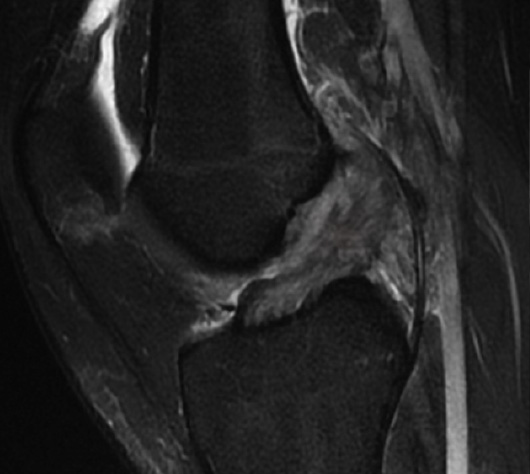

La resonancia magnética nuclear es un estudio altamente especializado, sensible y específico para visualizar las estructuras de la rodilla y sus lesiones. Es mediante este estudio que podemos respaldar el diagnóstico clínico, confirmarlo y detectar las lesiones asociadas (meniscos, cartílago y ligamentos).